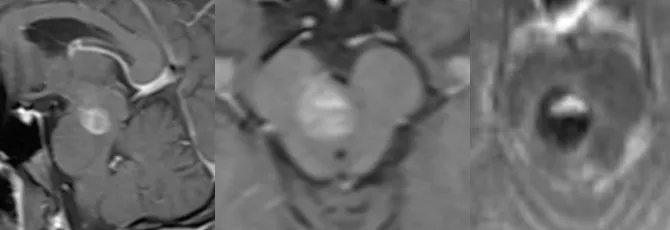

37岁的吴先生因脑干海绵状血管瘤急性出血首次就诊时,临床表现包括面部感觉麻木、言语清晰度下降、右手书写与打字功能丧失、左下肢行走稳定性减退等症状。在疾病初始治疗阶段,患者对手术干预方案表现出决策迟疑,选择了保守观察等待的治疗策略。然而临床病情进展并未按照预期方向发展——患者在较短时间内出现了突发性神经功能恶化:完全丧失行走能力、言语功能进一步受损、视觉清晰度下降等临床表现。"出血灶自行吸收"的理论预期与临床实际情况存在显著差异,取而代之的是血管瘤持续性出血活动与神经功能的急剧恶化过程。

这份跨越重洋的紧急医疗请求传递至德国。巴特朗菲教授在审阅最新影像学检查结果后明确判断:"脑内出血病灶范围明显扩大,同时患者临床症状也出现显著加重。毫无疑问这属于神经外科急症范畴,需要尽快安排手术治疗,我可以在下周时间窗口内安排手术操作。"

多数患者的临床病史显示,脑干海绵状血管瘤的出血事件具有反复发作、非一次性特点。随着出血次数增加,往往会出现再出血频率增高、症状加重趋势,神经功能障碍甚至可能转变为不可逆性损害。如果出血累及面神经核团区域,将导致面部瘫痪;如果影响感觉与运动神经传导束,将引起肢体麻木乏力症状。脑干体积仅相当于成人拇指大小,反复数次出血就可能导致整个脑干结构受压变形。